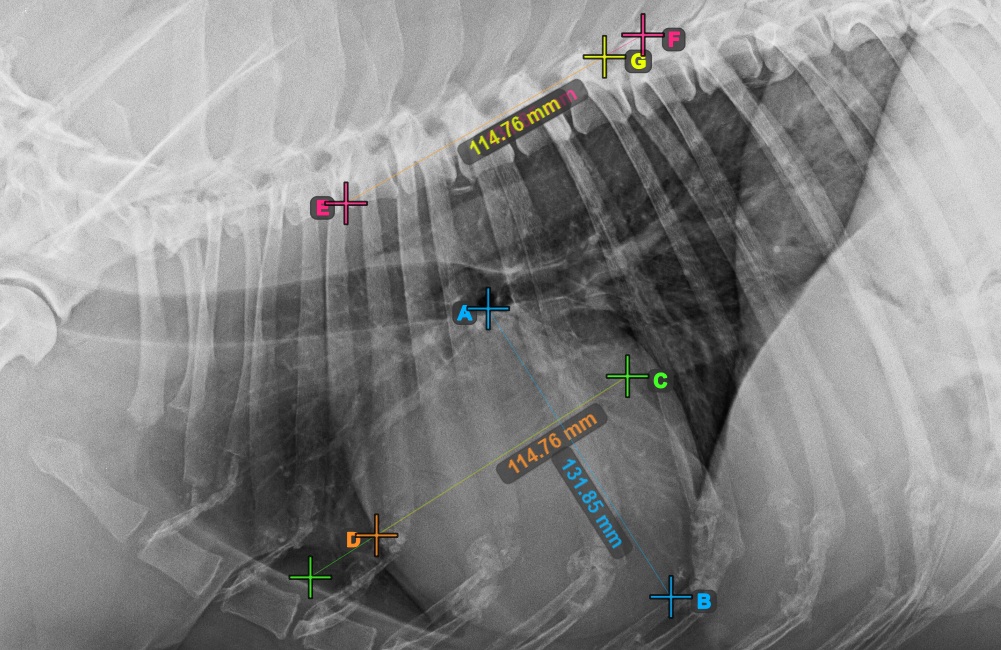

Starten Sie die Messung, indem Sie die Bifurcatio tracheae in der Nähe der Herzspitze markieren.

Das Bild unten zeigt die typische Platzierung des Punkts Bifurcatio tracheae.